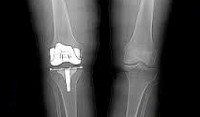

Первичная тотальная артропластика коленного сустава. Хирургическое вмешательство, при котором сустав, поврежденный или поврежденный вследствие болезни, заменяется искусственным имплантатом. Полное эндопротезирование называется потому, что во время операции заменяются все суставные поверхности колена. Тотальное эндопротезирование проводится при неэффективности консервативных методов лечения, невозможности восстановления функции сустава после внутрисуставных переломов или заболеваний коленного сустава (артроз, артрит, новообразования, асептический некроз тазобедренных мышей и ).

Вырезанные суставные поверхности заменяются протезами, которые прикрепляются к кости с помощью специального цемента. Чтобы обеспечить амортизацию и обеспечить легкое скольжение новых суставных поверхностей во время движения, между ними устанавливается полимерный вкладыш.

Хирургическое вмешательство проводится под общим наркозом или проводниковым наркозом. Суставные поверхности обнажены, их верхние части обрезаны. При условии сохранения здоровой костной ткани и сохранности связочного аппарата.Вырезанные суставные поверхности заменяются протезами, которые прикрепляются к кости с помощью специального цемента. Чтобы обеспечить амортизацию и обеспечить легкое скольжение новых суставных поверхностей во время движения, между ними устанавливается полимерный вкладыш.

Решение об операции принимается после рентгенологического исследования сустава и полного обследования пациента. Пациент обследуется и осматривается анестезиологом, при необходимости направляется на консультации к другим специалистам (терапевту, эндокринологу ). Выбор эндопротеза основан на внешнем осмотре и рентгенографических данных.